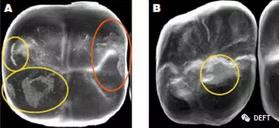

圖3  A圖:顯示了對頜牙在BruxZir全鋯冠上造成的磨損的平面,黃色圓圈代表復(fù)合樹脂和釉質(zhì),橙色圓圈代表瓷。B圖:顯示了對頜牙為鑄造金屬修復(fù)體時(shí),對切削類e.maxCAD單冠造成的磨損平面。兩種牙冠表面都有小的磨損平面,而且他們的對頜牙都顯示出了良好的結(jié)果。臨床上,對頜牙的每種材料(瓷、樹脂、釉質(zhì)、鑄造金屬)被磨損的程度幾乎是等同的。